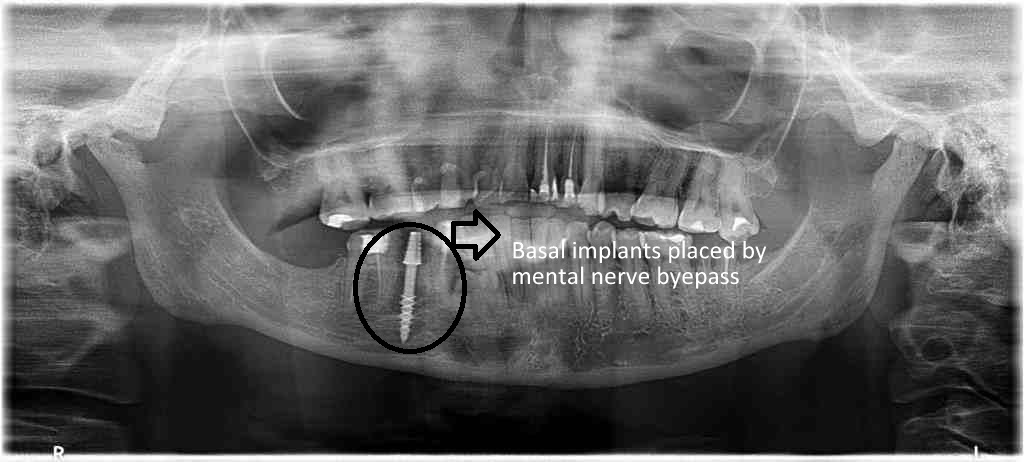

BASAL IMPLANT PLACEMENT BY MENTAL NERVE BYEPASS